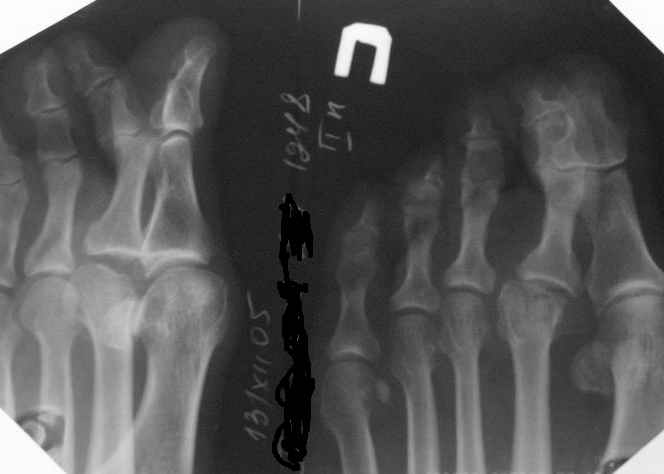

У меня была похожая пациентка - тоже с вальгусной деформацией, неуточненная травма 3 года назад. Обратилась по поводу болей в области головки 2 плюсневой кости, в течение 2-х месяцев. При осмотре - небольшая припухлость, движения в суставе в полном объеме, даже некоторая "разболтанность" отмечается. Боли усиливались в основном при ходьбе на каблуке, когда увеличивалась нагрузка на головку плюсневой кости. У неё были более выраженные изменения на Rg-грамме (во вложении), а здесь - только если в прямой проекции (справа) можно заподозрить некоторую уплощенность головки...

если бы речь шла о чистой остеохондропатии, то мне мысли Юлии Олеговны казались бы ближе всех к истине, но давайте обратим внимание на боковую проекцию: кто-нибудь видит какие-либо изменения, кроме углового смещения головки в подошвенную сторону?

Мне картина видится такой: жил себе пациент с молоткообразным ІІ пальцем, что характерно при такой вариации в длине I и II плюсневых костей, это и вызывало боли в ступне. Месяц назад "придавил" II пфс радиатором, получил перелом головки ІІ пястной кости с подошвенно-угловым смещением (приложение силы основной фаланги ІІ пальца), сейчас перелом почти сросся (линия перелома еще слегка прослеживается).